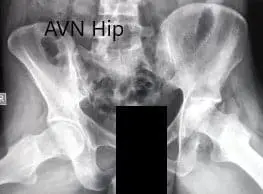

Preoperative X-ray of the pelvis with both hips in frog-legged lateral views